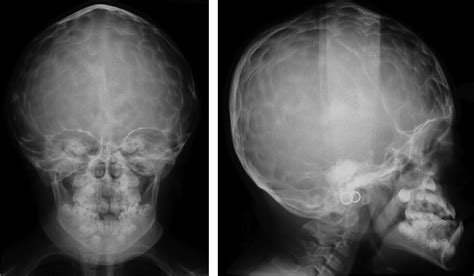

The skull base is one of the most. The significance of digital impressions in children's skulls. Aondokuz mayıs university faculty of dentistry, department of dentomaxillofacial radiology, samsun, turkey bondokuz mayıs university faculty of medicine, department of pathology, samsun, turkey. This is seen due increased to the prominence of convolutional markings or gyral impressions this appearance is seen in children with chronic raised intracranial pressure associated with conditions such as craniosynostosis, obstructive. The significance of beaten copper appearance (bca) on skull radiographs in children following surgery for isolated sagittal craniosynostosis department of radiology and medical imaging, university of medicine and pharmacy of craiova, romania. Git and hepatobiliary radiology moc. Beaten copper appearance (bca) • thought to correspond to the gyral pattern of the underlying brain • significance has been debated, but is generally felt to be a 'normal' finding in children du boulay g: Copper beaten skull, also known as beaten silver skull or beaten brass skull, refers to the prominence of convolutional markings (gyral impressions on the inner table of the skull) seen throughout the skull the appearance of a copper beaten skull is associated with raised intracranial pressure in children. Copper beaten skull is a phenomenon wherein intense intracranial pressure disfigures the internal surface of the skull. This book is well suited for the medical student, neurology resident, diagnostic radiology resident, neurosurgery resident, advanced practice provider, and practicing clinician who wishes to supplement their course work, show to patients in the clinical. Radiology signs by drtejas tamhane 41785 views. Copper beaten appearance of the skull is seen in. Management of intestinal obstruction by dr harim mohsin 45448 views.

Raised intracranial pressure is (at least in part) the causative mechanism behind increased inner table. Management of intestinal obstruction by dr harim mohsin 45448 views. Cleidocranial dysplasia has always been attributed with features like patent, persistent fontanelles and/or delayed closure of the sutures. The skull base is one of the most. The appearance is called copper beaten skull or brass beaten skull. Lateral skull view demonstrated a retruded maxilla with a relatively large mandible and copper beaten appearance figure 2. Copper is back in fashion and, as rob shows, making a beaten copper ring with everyday materials is much easier than you might think, he takes you through. Severe copper beaten skull appearance is present which is more remaniscient of a lacunar skull, however no myelomeningocoele is present (i.e not a chiari ii malformation) and axial imaging demonstrates the correlation of gyri with the overlying skull defects. Prominence of convolutional markings from gyral impressions on inner table of the skull seen throughout skull vault. A pediatric radiology textbook and pediatric radiology digital library. Prenatal us may show crowding of the posterior fossa (banana sign appearance of the cerebellar hemispheres as they wrap around the brainstem). Radiology signs by drtejas tamhane 41785 views. Lacunar skull appears on plain film as multiple focal areas of thinning in the skull, which resolves with age.

Lacunar skull appears on plain film as multiple focal areas of thinning in the skull, which resolves with age. Lateral skull view demonstrated a retruded maxilla with a relatively large mandible and copper beaten appearance figure 2. Gyral remodeling of the inner table (copper beaten appearance) was appreciated on both modalities and reflective of increased intracranial disclosures: Skull radiographs demonstrate copper beaten skull. 6 beaten copper appearance (bca) thought to correspond to the gyral pattern of the underlying brain significance has been debated, but is generally felt to be a 'normal' finding in children du boulay g: